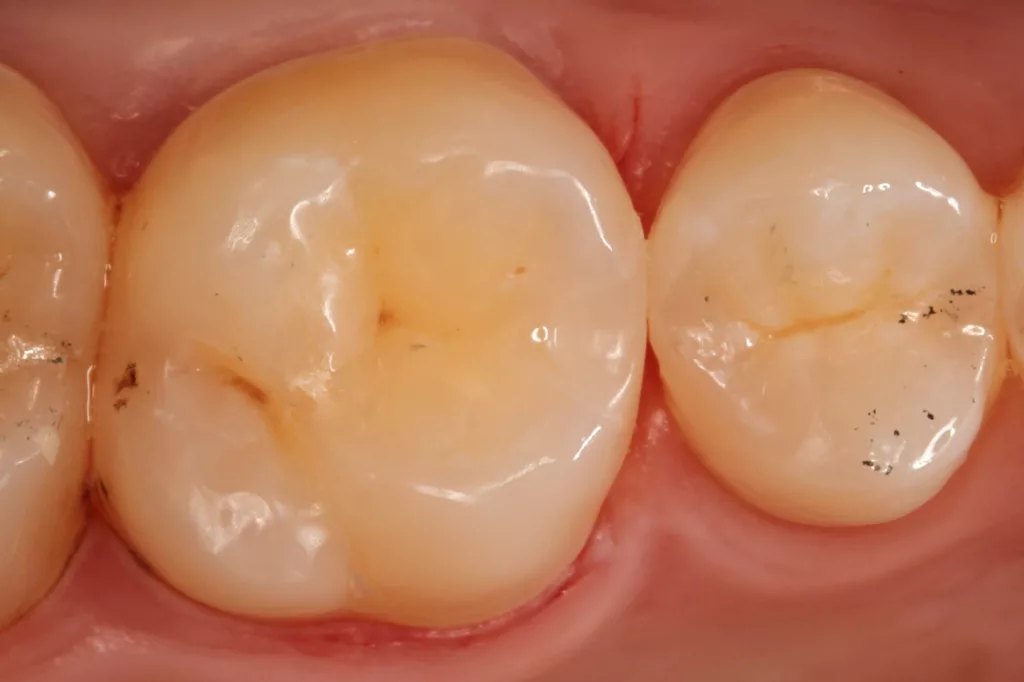

Fall 2: Versorgung einer Initialkaries an Zahn 14 und später an 15

Die 26 Jahre alte Patientin störte sich an der approximalen Lücke zwischen den Zähnen 14 und 15, da sich hier ständig Speisereste impaktierten. Bei der klinischen Inspektion fiel die Initialkaries distal an Zahn 14 auf (Abb. 7). Die Patientin wurde dahingehend beraten, den Spalt mit einer minimalinvasiven Kompositrestauration zu versorgen – bei zeitgleicher Exkavation der Karies an Zahn 14. Nach Exkavation und Präparation des Defektes (der sich als deutlich ausgeprägter präsentierte als anfangs angenommen) erfolgte identisch zu Fall 2 die Ausformung der Kavität mit einer Teilmatrize (Danville ultra thin flex), einem Kunststoffkeilchen (G-Wedge) und der Separation mit einem NiTin-Prämolaren-Spannring (re-invent, Abb. 8).

Teilmatrizensysteme stellen heutzutage die erste Wahl in der Gestaltung anatomischer Kontaktflächen dar [22]: Sie garantieren korrekte anatomische Formen, straffe Approximalkontakte und belastungsoptimiert ausgeformte Randleisten [74–76]. Nach der adhäsiven Vorbehandlung (G2 Universal, GC, total etch) wurde der Defekt identisch zum vorherigen Fall mit dem niedrigviskösen Visalys Bulkflow in einem Zug aufgefüllt und mit der Sondenspitze ausmodelliert (Abb. 9). Die Aushärtung (Elipar Deep Cure) erfolgte erneut standardisiert für jeweils 20 Sek.: einmal okklusal zentral nach Einbringen des Bulkflow-Materials und je einmal als Nachhärtung nach Abnahme der Matrizen-Verschalung aus bukkaler und erneut okklusaler Richtung mit genau auf der Randleiste positioniertem Lichtgerät. So wird mit Sicherheit eine suffiziente Aushärtung des 4 mm tiefen Defektes gewährleistet.

Die Abbildung 10 zeigt das Behandlungsergebnis unmittelbar nach Ausarbeitung und Politur (Diacomp Plus Twist, EVE), die Abbildung 11 bei einer weiteren Kontrolle nach sechs Monaten. In diesem Kontrolltermin wurden dann im routinemäßigen, zwei- bis dreijährigen Intervall Bissflügelröntgenaufnahmen zur Kariesdiagnostik angefertigt. Auf der Röntgenaufnahme zeigt sich die neue Visalys-Bulk-Flow-Restauration als randdicht, anatomisch korrekt geformt und ausreichend röntgenopak (Abb. 12). Die Schmelzläsion mesial an den Zähnen 15 und 16 erschien nicht therapiebedürftig, da die Oberfläche intakt war, wohl aber die versteckte Dentinläsion distal an dem Zahn 15. Der Defekt wurde in einem weiteren Termin identisch mit denselben Materialkombinationen und identischem Polymerisationsprotokoll versorgt (Abb. 13 bis 15).